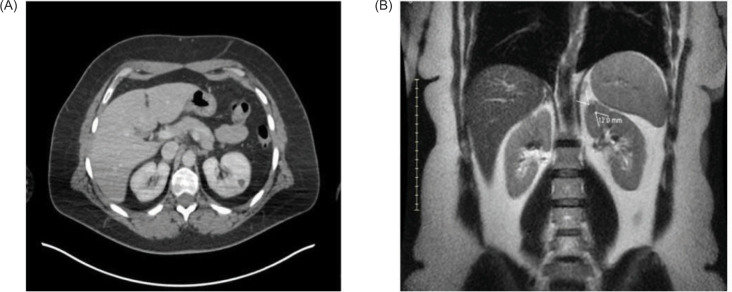

眼部黑色素瘤是黑色素瘤的一种形式,它很少提供可操作的突变来进行全身治疗,并且相对具有放射抗性。因此,手术是局部疾病的主要治疗方法,可以考虑治疗少转移性疾病。我们报告一例眼部黑色素瘤在初次诊断并接受眼内近距离放射治疗9年后复发并单发肾转移。经过多学科的讨论,患者接受了部分肾切除术,她的单发肾转移。患者在部分肾切除术后持续随访3.5年。在确定多灶性疾病后开始全身治疗之前,她再次接受了手术治疗,原因是单纯转移到乳房。鉴于黑色素瘤和其他形式的癌症治疗前景的迅速变化,我们建议对转移性侵犯靶器官的患者进行跨学科管理。

Ocular melanoma is a form of melanoma that rarely offers actionable mutations for treatment with systemic therapy and is relatively radioresistant. As such, surgery is the mainstay of treatment for localized disease and can be considered for oligometastatic disease. We present a case of ocular melanoma that recurred with a solitary renal metastasis 9 years after initial diagnosis and treatment with intraocular brachytherapy. After multidisciplinary discussion, the patient underwent a partial nephrectomy for her solitary renal metastasis. The patient continued in follow-up 3.5 years after partial nephrectomy. She was treated again surgically for a solitary metastasis to the breast before initiation of systemic therapy once multifocal disease was identified. We suggest interdisciplinary management of patients with metastatic involvement of target organs, given the rapidly changing treatment landscape for melanoma and other forms of cancer.